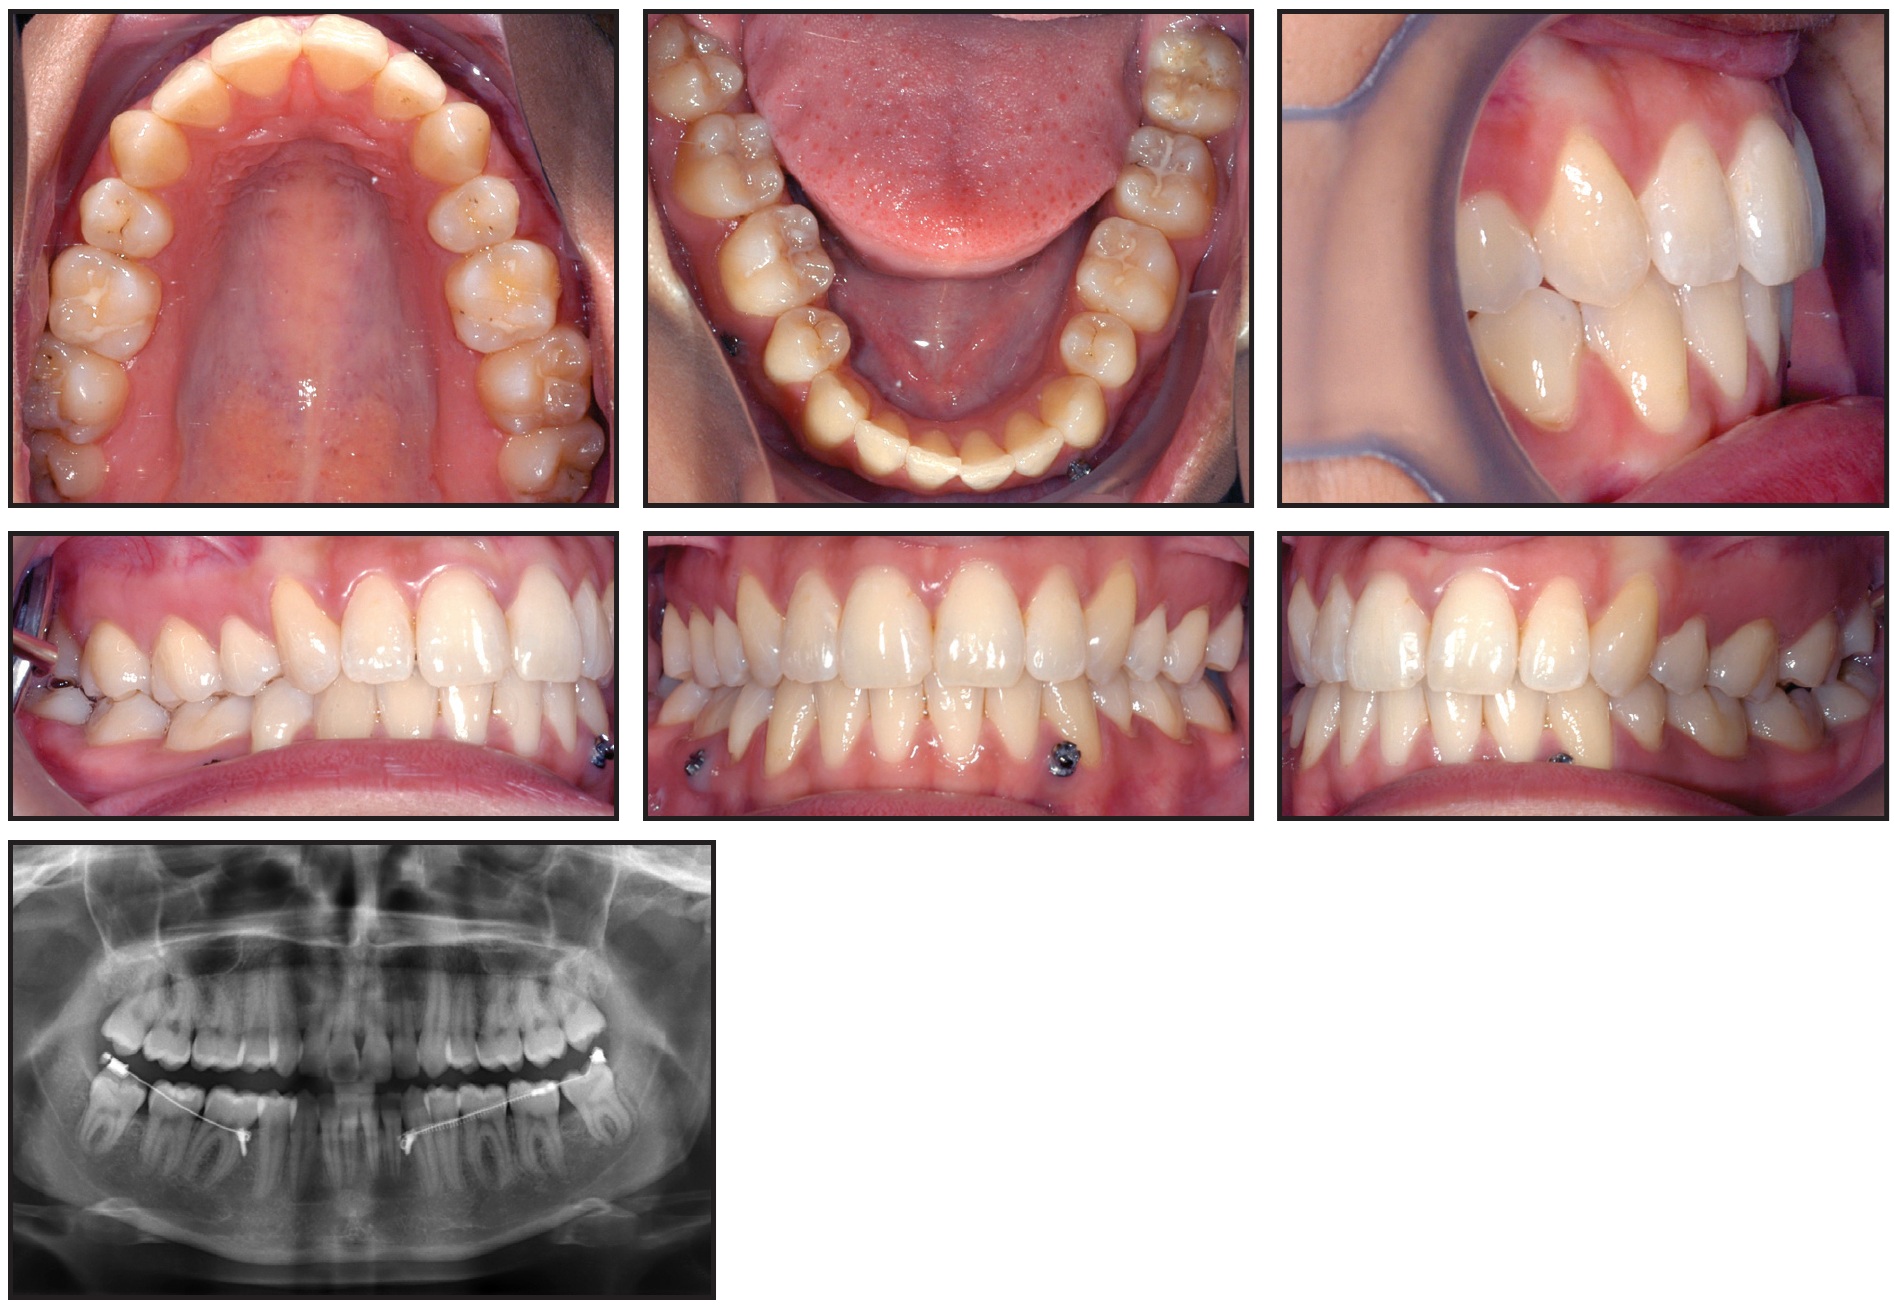

This 22-year-old male had completed comprehensive orthodontic treatment two years earlier (Fig. 3).

Fig. 3 Case 1. 22-year-old male patient with mesially impacted lower right third molar two years after completion of previous orthodontic treatment.

A panoramic x-ray showed that all third molars were present, with the lower right one mesially impacted. A mini-implant was inserted between the roots of the lower right premolars, and, after minimal exposure of the distal cusps, a tube was bonded. The uprighting mechanics described above were applied, delivering a counterclockwise moment to the third molar (Fig. 4).

Six months later, with the third molar fully upright, the appliance was removed (Fig. 5). The lower right third molar was in stable occlusion with its antagonist, but the upper third molars had not yet erupted. Contrary to expectations, the lower left third molar remained in its original vertical position and may require active alignment.